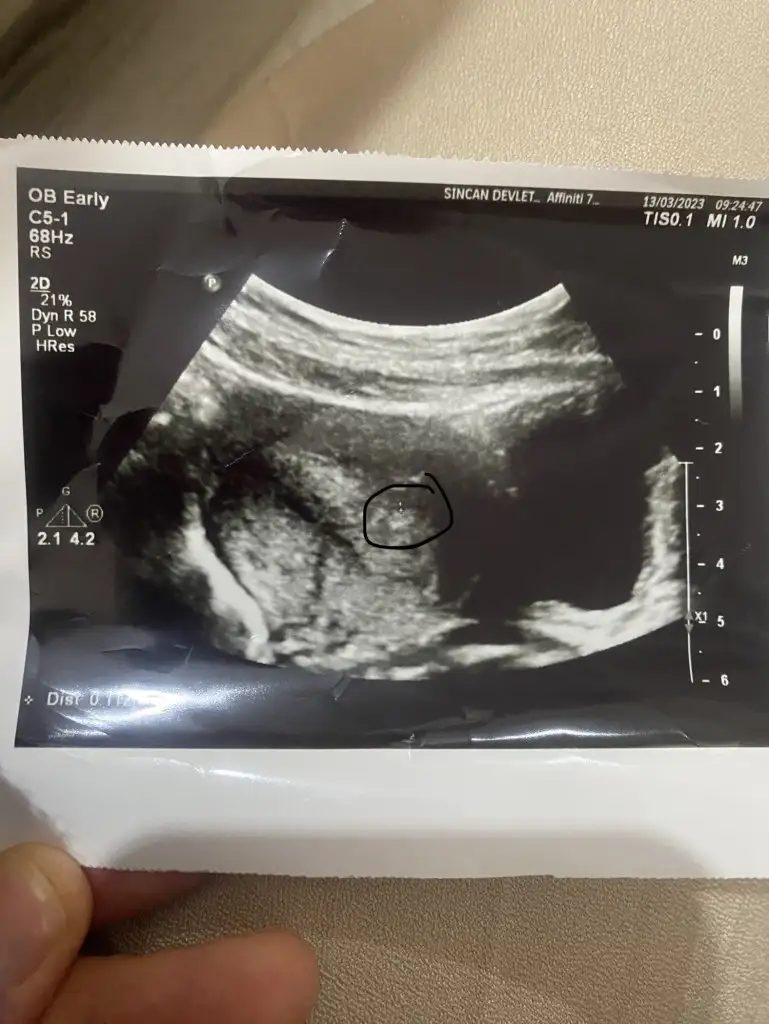

Kızlar hastaneden geliyorum doktor ultrason da baktı küçük bi kese görüyorum dedi fotoğrafı ekledim adetten 4 gün geçti

doktor küçük bir kese görüyorm dedi

Yine kan testi idrar falan istedi yarın gel bakalım sonuçlara dedi en son 5 gün önce vermiştim foto attım ultrason